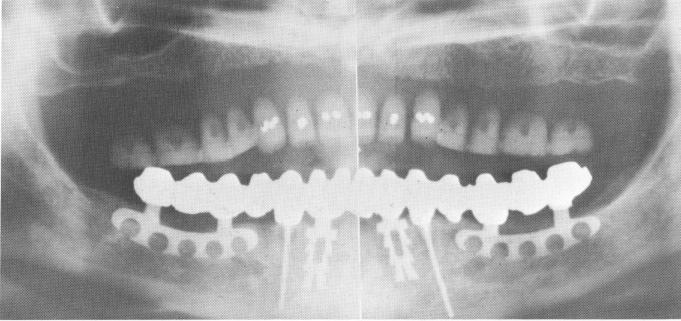

Fig. 13-59. A, Endodontic stabilizers were introduced into the cuspids. The teeth and implants are protected from the saliva with the use of rubber dams. B, An immediate postoperative radiograph.

Fig. 13-60. Six months later than Fig. 13-59. Notice that the Kri paste seen around the apices of the stabilizers in Fig. 13-59 has been completely resorbed.

3 Immediate postoperative x ray after seating endodontic stabilizers